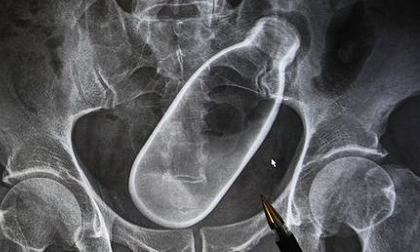

Nhét cả chai nước vào hậu môn để... chữa táo bón

Một người đàn ông đã tự ý chữa bệnh cho mình bằng một hành động thiếu hiểu biết.